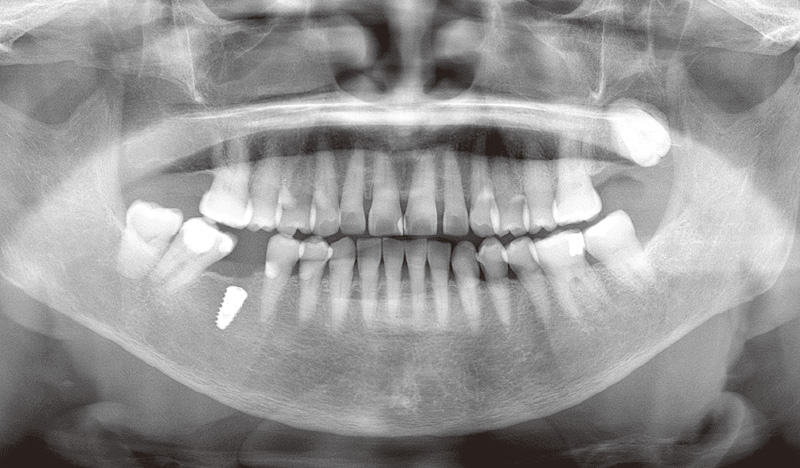

症例1-1 70代女性。₆欠損で来院。カウンセリングでは、ブリッジやインプラントなど、治療の選択肢を提示した。 -

症例1-4 顎骨を露出させ、ドリリング後にインプラントを埋入。(「ルナビューショット」で撮影した動画より抽出) -

症例1-5 一次手術を終えた現在の状態。近々二次手術を予定している。 -